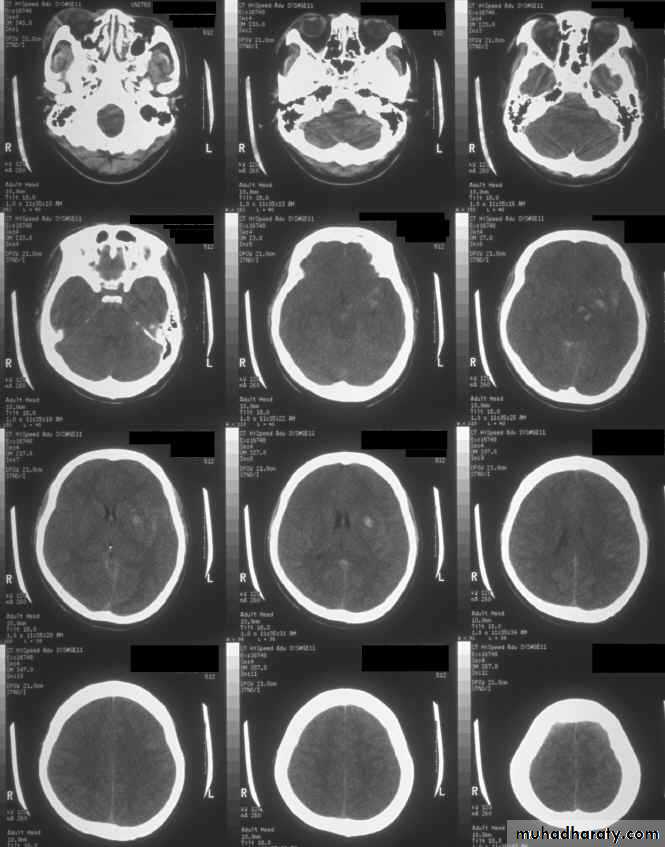

1. Diffuse Axonal Injury

Prolonged post-traumatic state in which there is loss of consciousness from the time of injury that continues beyond 6 hours.

Occurs as a result of mechanical shearing at the grey-white matter interface.

This causes disruption and tearing of axons, myelin sheaths and blood capillaries.

Severity can range from mild damage with confusion to coma and even death.